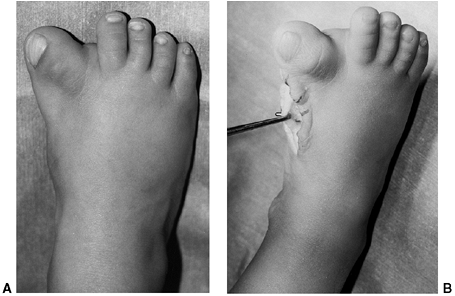

tight medial structures, including the posterior tibial tendon and

plantar soft tissue. An attempt is also made to strengthen the peroneal

muscles by stimulation. Adhesive taping (Fig. 30.13)

is applied to supplement the exercise and maintain correction that is

gained by stretching. Daily treatments are continued for 2 months. The